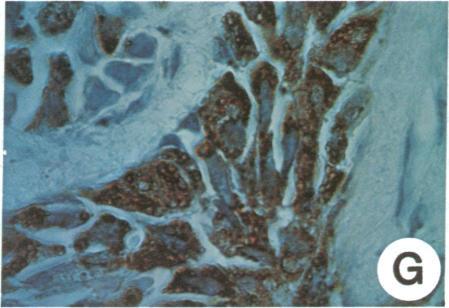

Lymphocytes from lymph nodes obtained at mastectomy in breast cancer patients have been fused with murine nonproducer myeloma cells to obtain human-mouse hybridoma cultures that synthesize human monoclonal antibodies. To date, 52 hybridoma cultures synthesizing either human IgG or human IgM have been obtained from lymph nodes of 13 patients. Ig production was stable in many of these cloned cultures through 60-200 days of observation. Levels of human Ig synthesis ranged from 0.1 to 20 microgram/ml of supernatant fluid. The immunological reactivities of the human Igs were assayed on tissue sections by using the immunoperoxidase technique. Several of the human monoclonal antibodies demonstrated preferential binding to human mammary tumor cells. One human IgM monoclonal antibody was used to discriminate between mammary carcinoma cells (from 55 of 59 patients) and normal mammary epithelial cells, stroma, or lymphocytes of the same breast. Decreased binding to some of the benign breast tumors tested and to selected non-breast adenocarcinomas was also observed. This same human monoclonal antibody, however, reacted significantly with metastatic mammary carcinoma cells in lymph nodes of breast cancer patients, with no binding to normal lymphocytes or to stroma of the same node. These studies demonstrate that stable clones of human-mouse hybridomas can be generated by using lymph nodes of mastectomy patients and that clones can be selected which synthesize human monoclonal antibodies reactive with human mammary carcinoma cells.

已将乳腺癌患者乳房切除术中获取的淋巴结中的淋巴细胞与小鼠非分泌型骨髓瘤细胞融合,以获得能合成人单克隆抗体的人-鼠杂交瘤培养物。迄今为止,已从13名患者的淋巴结中获得了52种合成人IgG或人IgM的杂交瘤培养物。在60至200天的观察期内,许多这些克隆培养物中的Ig产生稳定。人Ig合成水平范围为每毫升上清液0.1至20微克。通过免疫过氧化物酶技术在组织切片上测定了人Ig的免疫反应性。几种人单克隆抗体显示出对人乳腺肿瘤细胞的优先结合。一种人IgM单克隆抗体用于区分乳腺癌细胞(59例患者中的55例)与同一乳房的正常乳腺上皮细胞、基质或淋巴细胞。还观察到对一些测试的良性乳腺肿瘤和选定的非乳腺腺癌的结合减少。然而,同一种人单克隆抗体与乳腺癌患者淋巴结中的转移性乳腺癌细胞有显著反应,与同一淋巴结中的正常淋巴细胞或基质无结合。这些研究表明,利用乳房切除患者的淋巴结可以产生稳定的人-鼠杂交瘤克隆,并且可以选择出能合成与人乳腺癌细胞反应的人单克隆抗体的克隆。